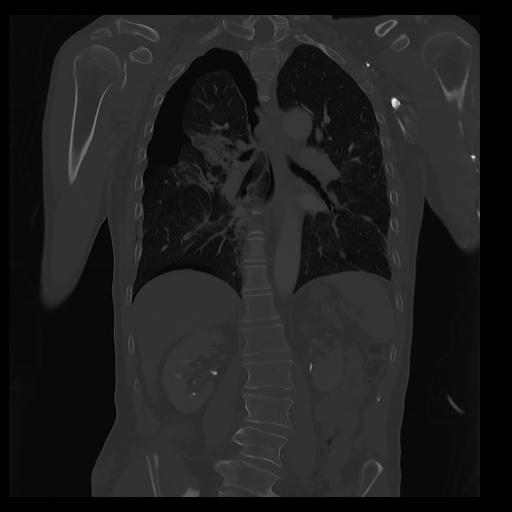

32 PULMON,CE,Coronal,3.000,PULMON,Coronal,